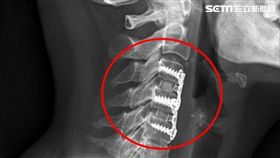

胸口悶痛無法躺睡 竟是頸椎間盤破裂

胸悶、胸痛,甚至無法躺平入睡的症狀持續一年多,楊小姐...